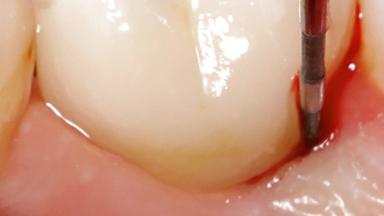

Due to their promising clinical performance, zirconia implants have recently become popular alternatives to titanium implants, particularly for areas with high esthetic demands (Holländer and coworkers 2016; Roehling and coworkers 2016; Lorenz and coworkers 2019). However, regardless of the reported high survival and success rates, zirconia implants were affected by peri-implant diseases over the short observation period, suggesting the importance of treating peri-implant diseases at zirconia implants (Becker and coworkers 2017). In their case, Frank Schwarz and Ausra Ramanauskaite present 3-year results following mechanical debridement alongside Er:YAG laser monotherapy.